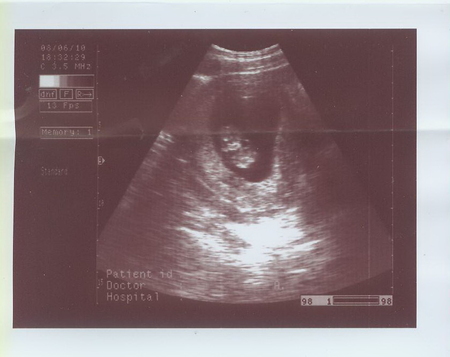

Были на УЗИ 08.06.2010 в МедЦентрСервисе на Курской. Очень понравилось.

С малышом все в порядке, размеры соответствуют норме. Толщина воротниковой зоны 1мм.

Сказал, что Малыш непоседа :) Кувыркался там, как акробат настоящий :)

Срок по УЗИ - 10 недель 3 дня.

Распечатал три фотографии!